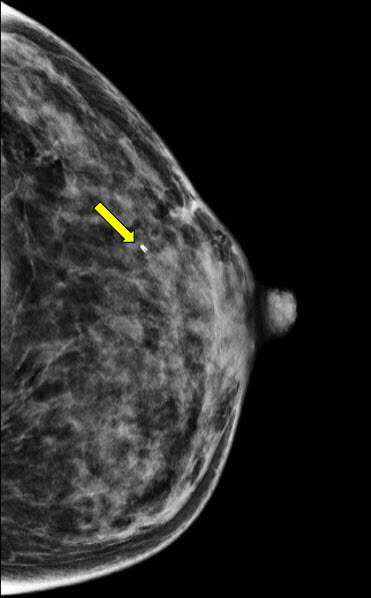

• Identify the biopsy site and determine lesion location using the grid localizer and depth within the breast from the grid (fig 2). Depending on institution, biopsy targeting software and/or post-processed images (such as subtracted images or reformatted images) may be used.

Procedure MRI Guided Breast biopsy Figure 2

Figure 2. Sagittal T1-weighted fat saturated post contrast images demonstrate the biopsy target, a focus of enhancement.